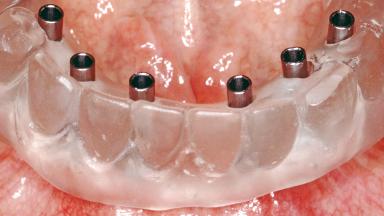

Conventional Loading of Six Implants in the Mandible and Final Restoration with a Full-Arch Metal-Ceramic FDP

A 68-year-old, completely edentulous male patient presented for evaluation and treatment options. He reported excellent general health and was taking no regular medication. He had been edentulous for approximately 12 years, having lost his teeth to periodontal disease and dental caries. The patient’s chief complaint was incompetent function. His secondary concerns included his appearance and the desire for a predictable outcome. He attributed his reduced functional capacity to his lower complete denture, which he described as poor. He was particularly concerned with the denture’s instability and poor fit. In general terms, he was satisfied with the maxillary complete prosthesis. The maxillary prosthesis was characterized by adequate retention, stability, and support, although the fit was considered less than ideal.

# of Implants 6

Type of Implants One-Piece

Defining Characteristics Fully edentulous lower jaw to be rehabilitated with an implant-borne fixed dental prosthesis

Retention Screw-retained, with 4 or more splinted implants Screw-retained, with 4 or more splinted implants